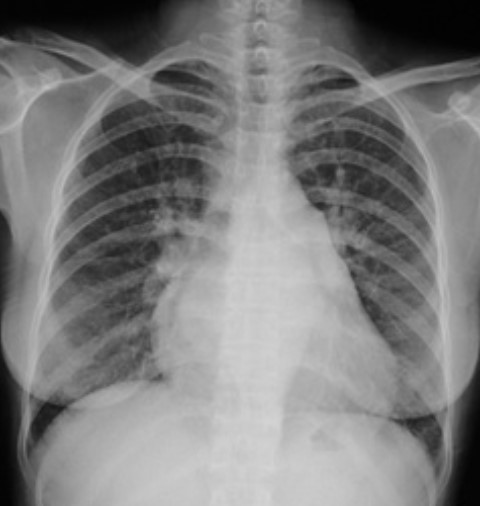

3.根据下图请做出正确诊断

A.正常心脏

B.心肌病(普大心)

C.风湿性心脏病(梨型心)

D.主动脉型心(靴型心)

答案提示:【该题针对“ X线-心脏增大(二尖瓣型、主动脉型和普大型) ”知识点进行考核】